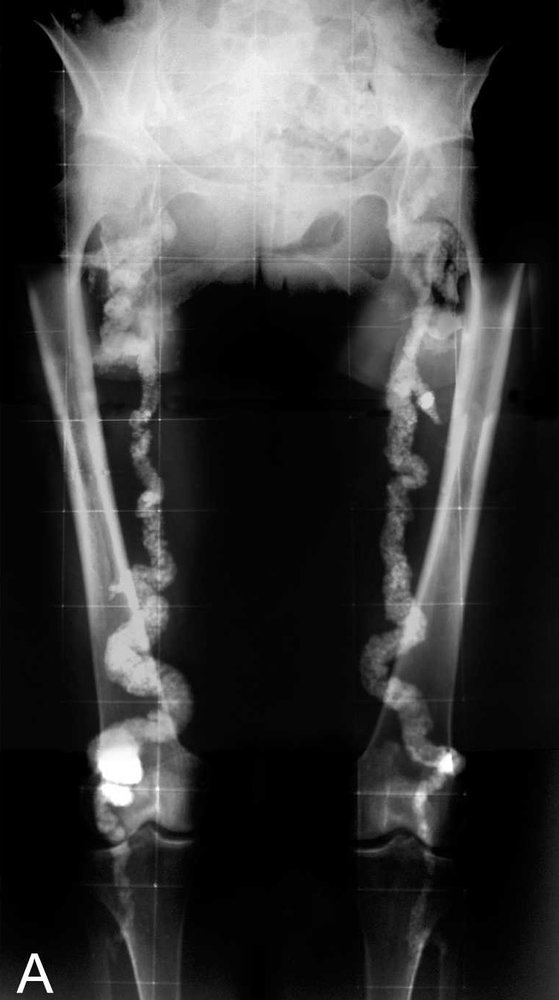

Monckeberg arteriosclerosis

- A form of arteriosclerosis characterized by dystrophic calcification of the tunica media and internal elastic lamina

- There is no blood flow obstruction.

- Mainly affects medium-sized arteries

- Causes: diabetes mellitus and/or progressive kidney disease

- X-ray: pipestem appearance